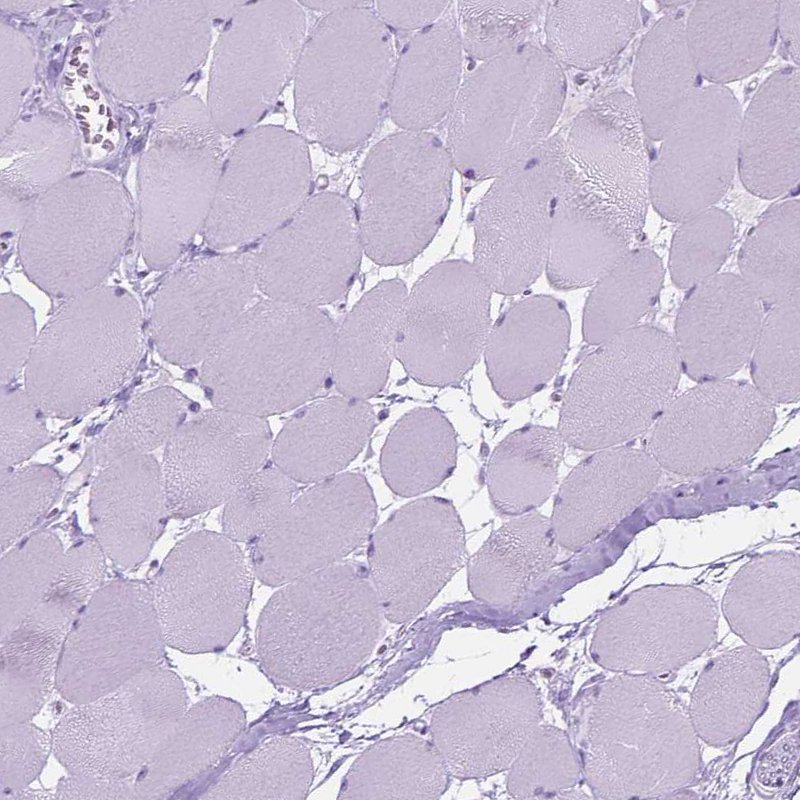

Immunohistochemistry analysis in human endometrium and skeletal muscle tissues using HPA012867 antibody. Corresponding HTR2B RNA-seq data are presented for the same tissues.